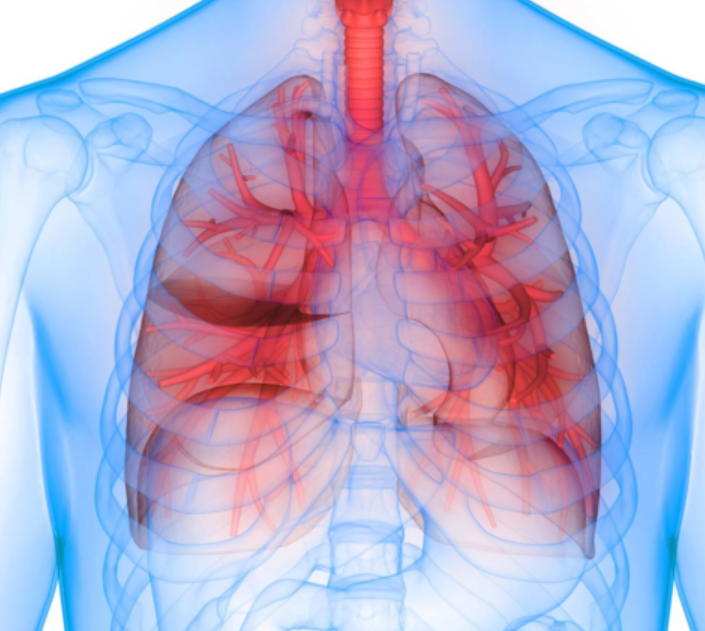

このセミナーは、要介護の前段階“フレイル”を合併するリスクの高い、慢性閉塞性肺疾患(COPD)の早期診断・治療の重要性を考えるという主題でした。

これに対し、同セミナーで講演した奈良県立医科大・呼吸器内科学講座の室繁郎教授は、「思い切ってたばこはスパッとやめた方がいい。肺機能は年々低下していくものなので、検査は年に1度くらい定期的にして欲しいです」と呼びかけました。